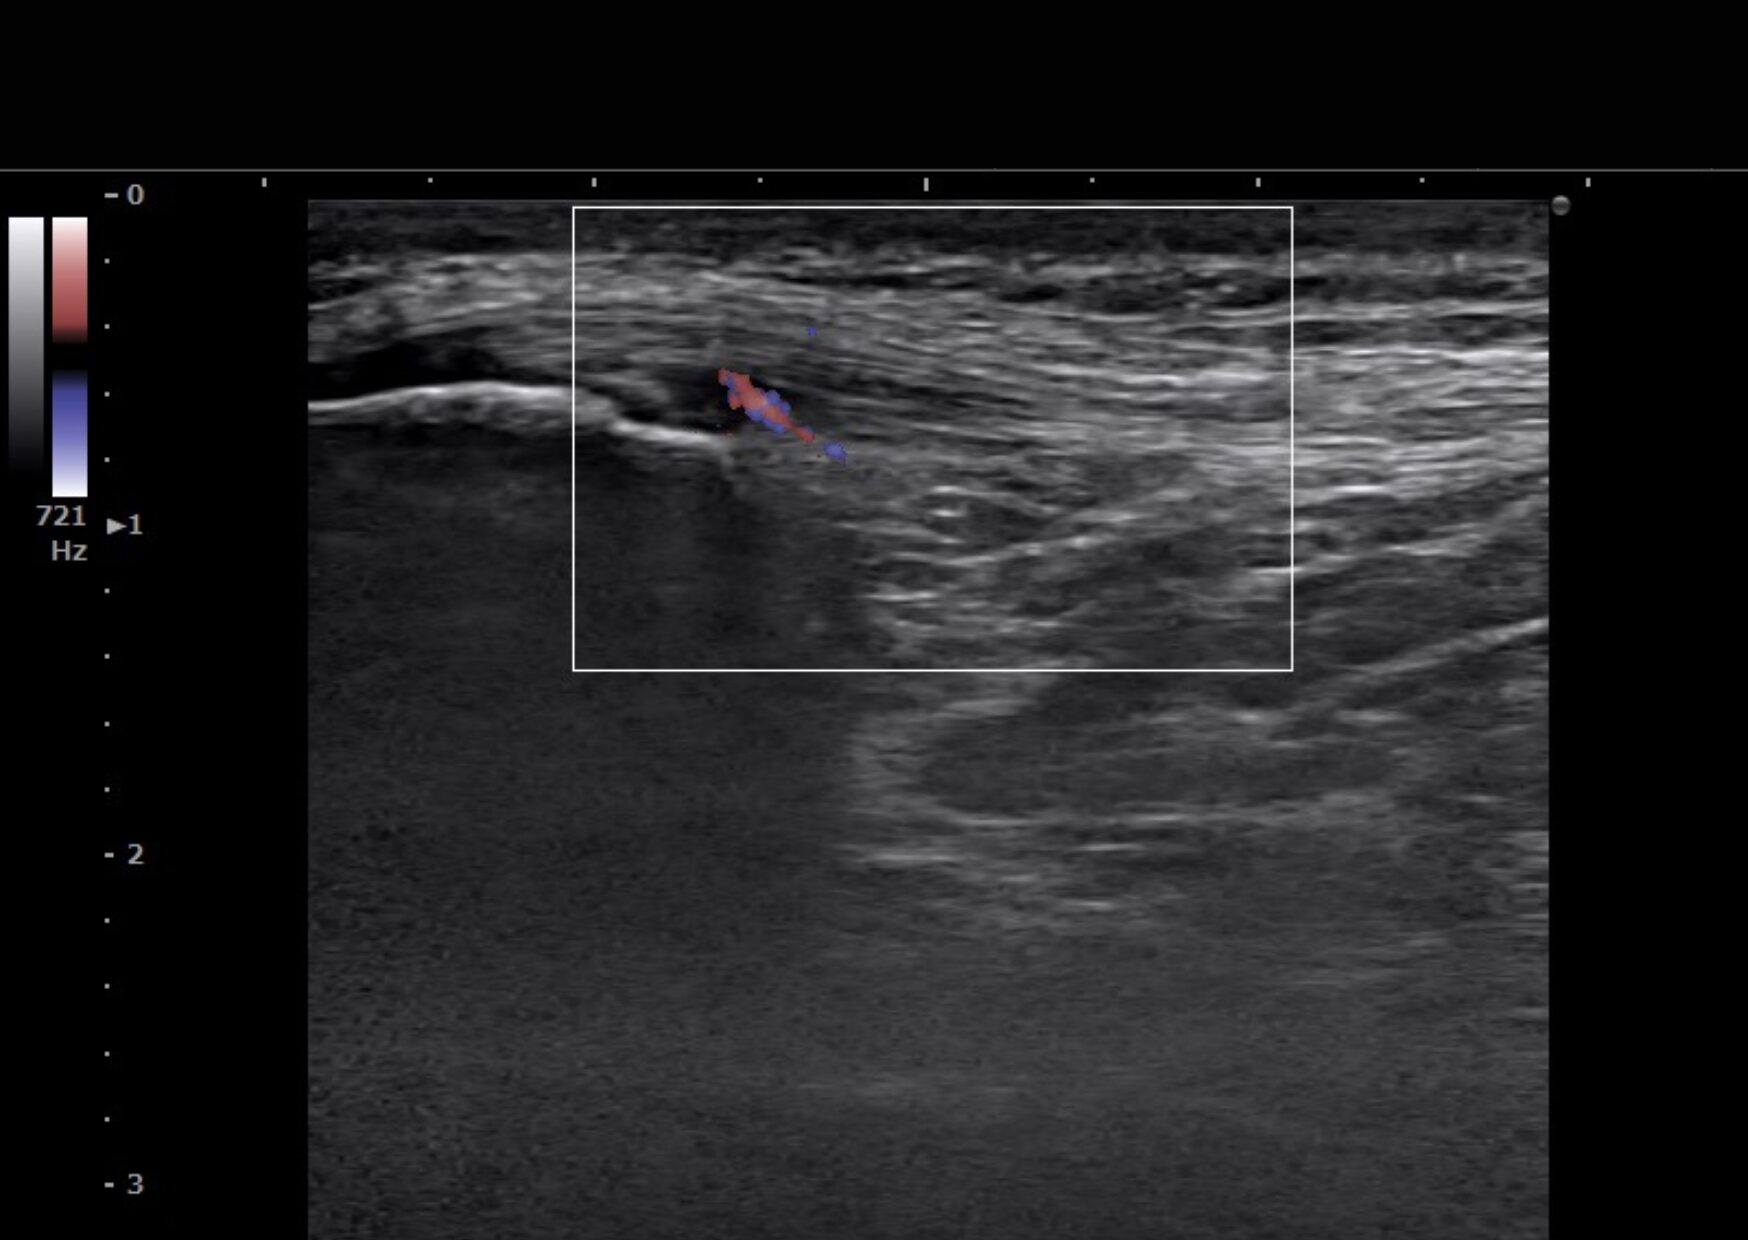

Case 02:膝蓋靭帯炎(ジャンパー膝)

着地の衝撃で「膝が抜ける」感覚。

膝蓋靭帯炎のドップラーエコー画像

▲ ドップラー機能による血流診断。赤い信号が炎症の火種(活動期)をリアルタイムに捉えています。

大学生のバスケットボール選手。着地時に体勢を崩して以来、膝の前面の腫れと、歩く時に膝がガクンと抜ける防御反応が出ていました。

【ドップラー機能による可視化】

当院のエコーは血流信号を捉える「ドップラー機能」を搭載。靭帯の付着部で火種のように燃え上がる炎症反応をリアルタイムで確認しました。

アプローチと結果: 炎症のピークを特定しピンポイントで消炎処置を実施。わずか1週間で「膝の抜け感」が消失しました。